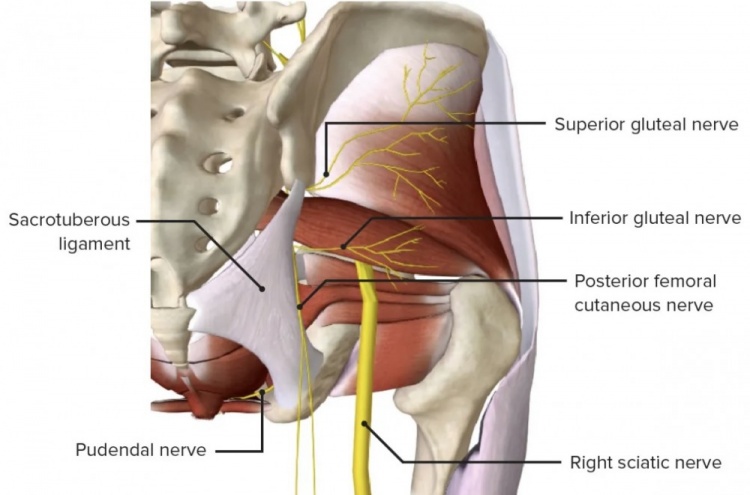

这一术语来源于坐骨神经,它从脊柱发出,沿着腿向下延伸,并在途中分出许多分支。

就勒布朗而言,在球队声明他患有坐骨神经痛之前,据说他正在应对“臀部神经刺激”的问题,这指的是构成髋部和下背部的臀肌。这些肌肉由多条神经支配。

基于以上信息,我们知道勒布朗可能正在应对高位神经刺激问题。如果他确实遭受的是坐骨神经痛,而不是一个笼统的诊断,这或许是一个积极信号,因为通常情况下,坐骨神经痛越严重,疼痛感会越往腿部下方延伸(远端),而不是集中在背部区域(近端)。